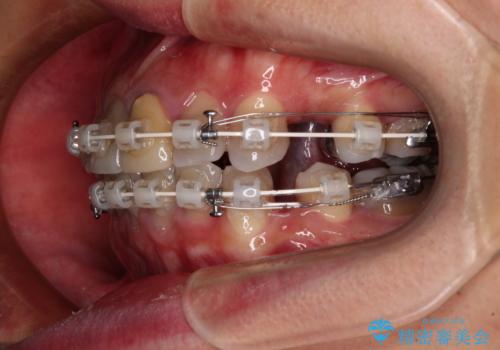

- 矯正装置

- 審美装置

- 2年3ヶ月

- 10-30回

- 飛び出した前歯を気にして来院された患者様です。

口元を引っ込めるために上下左右の第一小臼歯4本を抜歯することとしました。

速やかに治療を進めたいとのことで、表側のワイヤー装置で矯正治療を行うこととしました。